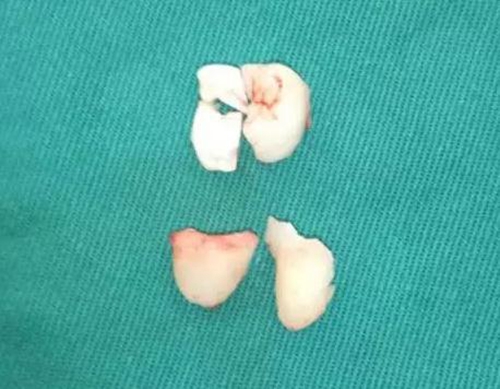

使用彎機(jī)加固美拔牙長柄車針,沿冠邊緣去除遠(yuǎn)中及頰側(cè)骨,完全去骨后,用彎機(jī)沿冠正中線分牙,完全分開后,挺患牙,這時的48稍微有些動度,但因近遠(yuǎn)中骨阻力較大,無法從遠(yuǎn)中向脫位。

使用普通手機(jī)加裂鉆沿遠(yuǎn)中冠中間磨除大部分冠組織,取出。

使用彎機(jī)開始分殘冠,使牙根近遠(yuǎn)中向的分開,使用牙挺挺松后,取出遠(yuǎn)中根。

去冠近中的骨壁,挺出之前分離出的殘冠,分次取出近中牙根,取刮匙刮牙槽窩。探查是否有剩余牙體組織。